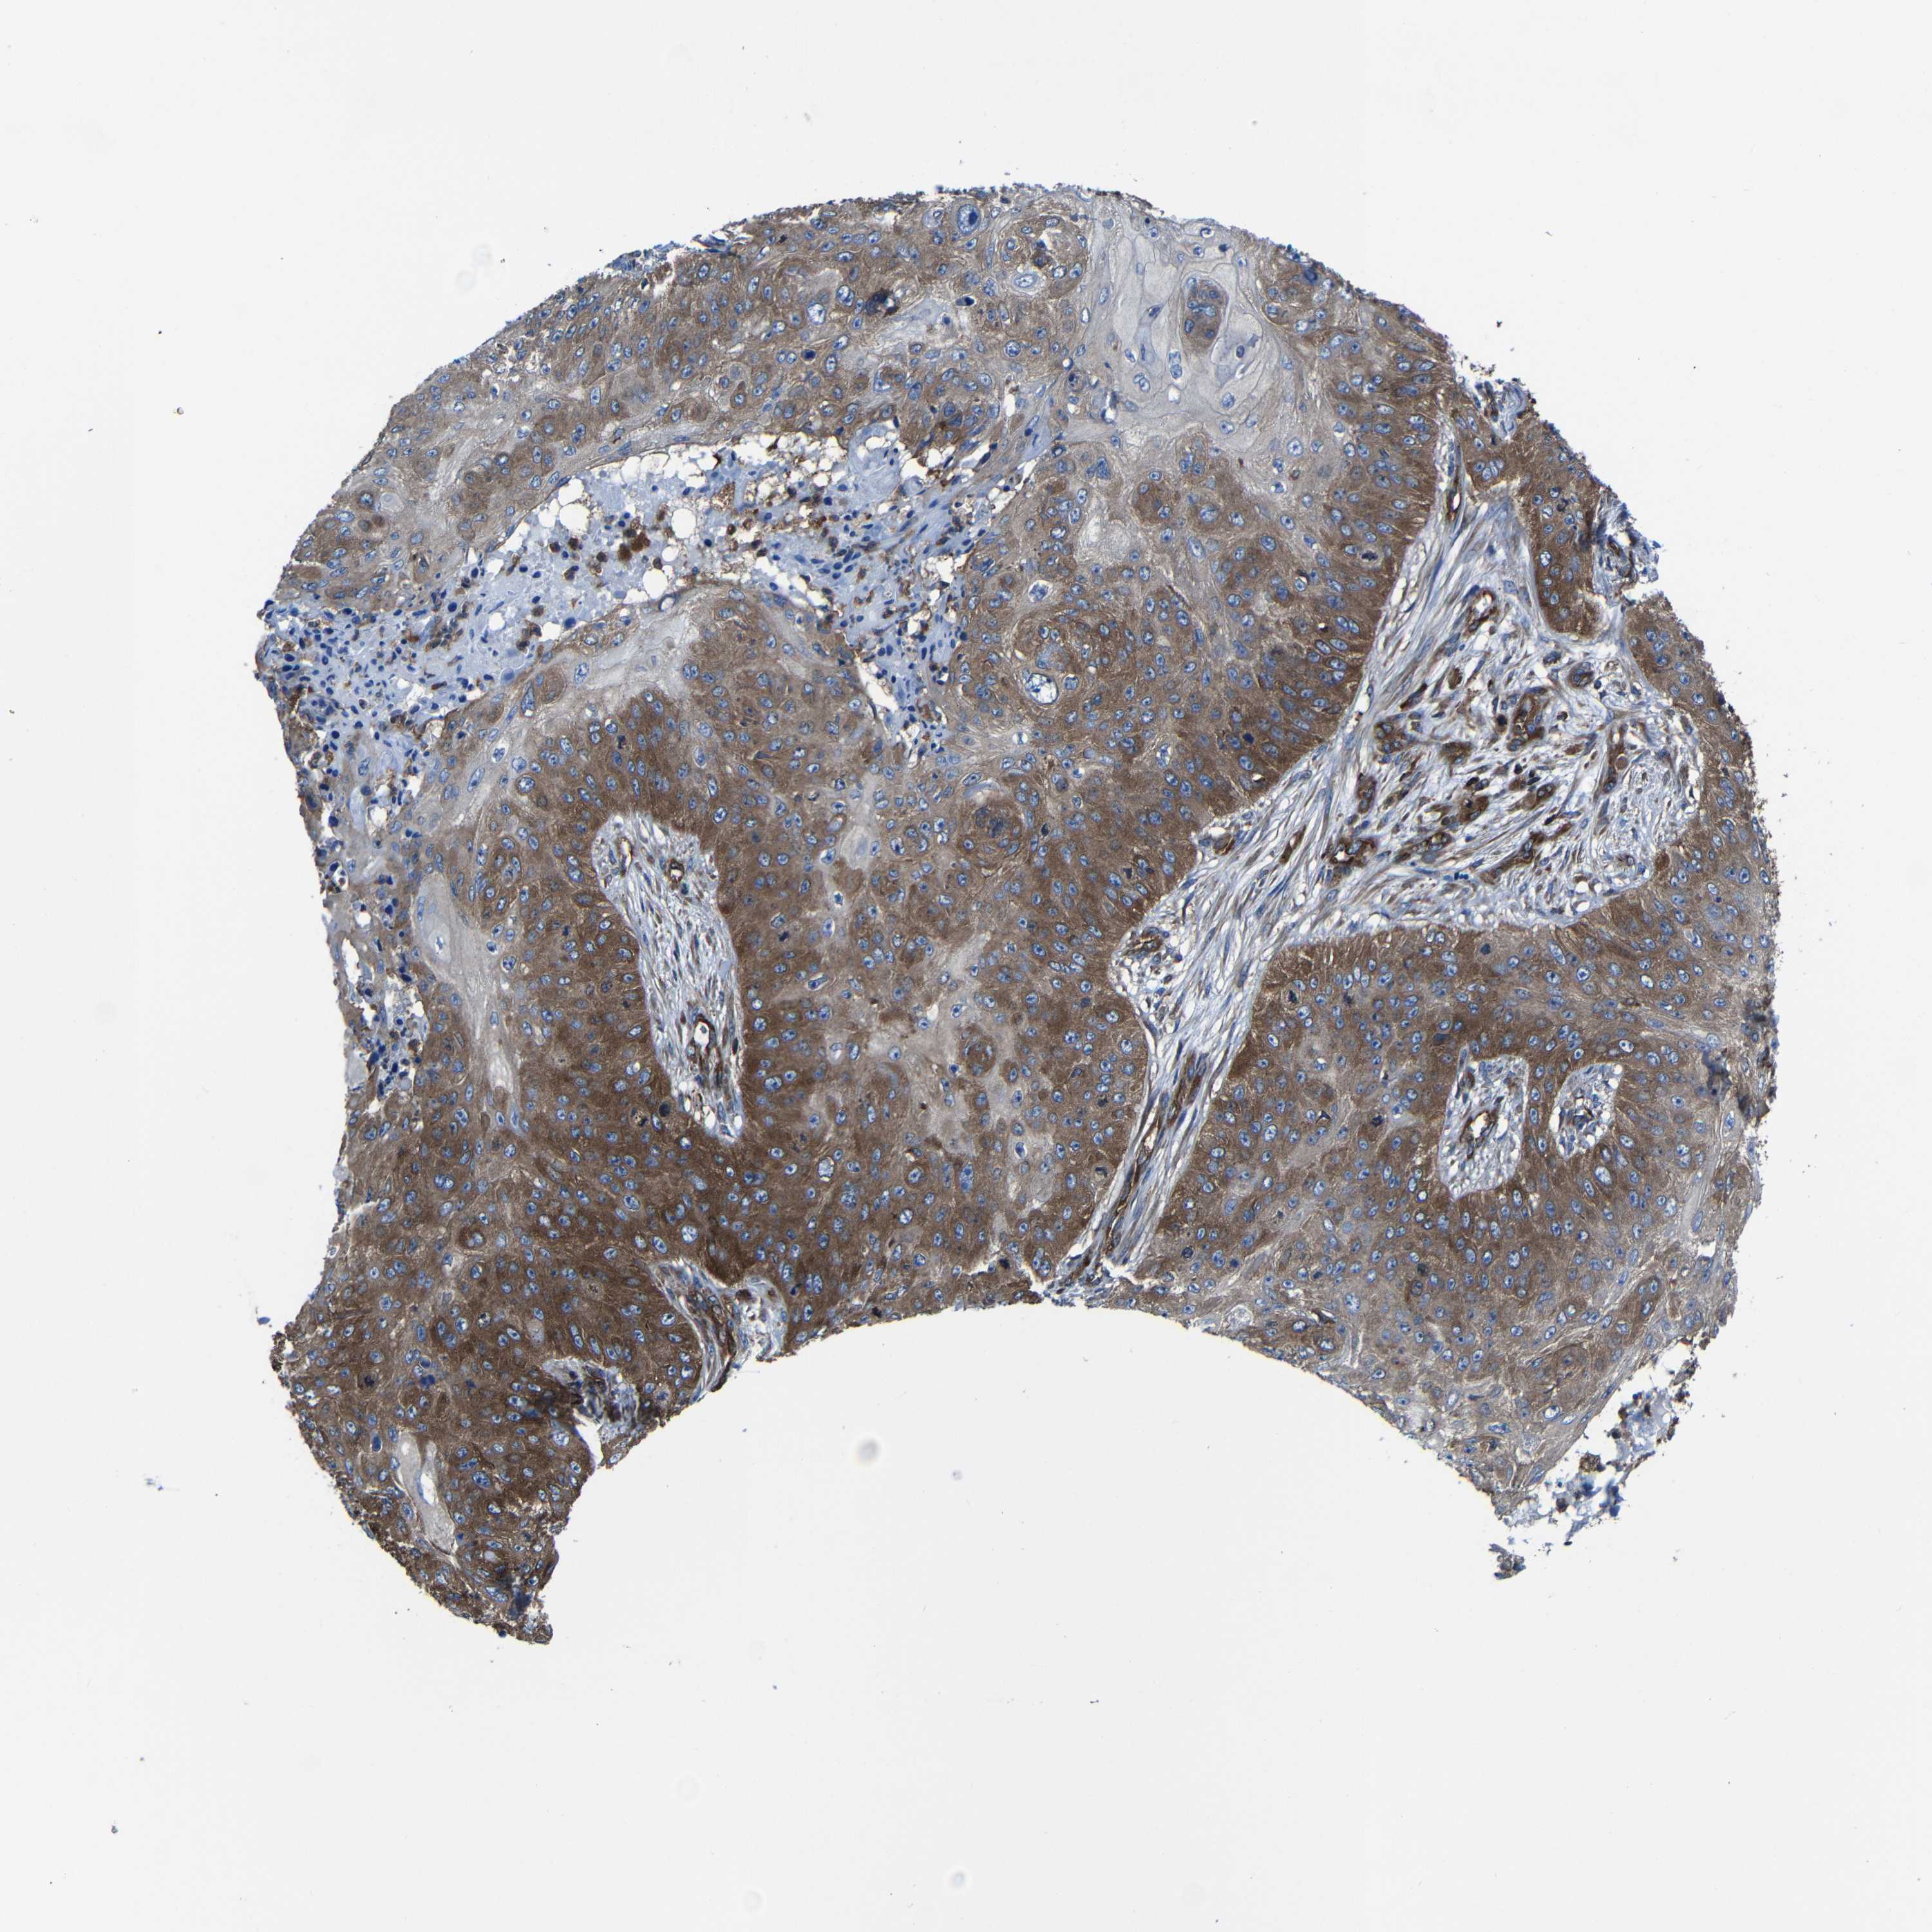

CANCER SKIN CANCER Show tissue menu

Basal cell and squamous cell cancer

SKIN CANCER - Protein expressioni

A mouse-over function shows sample information and annotation data. Click on an image to view it in a full screen mode. Samples can be filtered based on level of antibody staining by selecting one or several of the following categories: high, medium, low and not detected. The assay and annotation is described here.

Each image is clickable and will lead to virtual microscopy that enables deeper exploration of all samples and also displays staining intensity scores, fraction scores and subcellular localization as well as patient and tissue information for each sample.

Antibody HPA012924

Squamous cell carcinoma, NOS